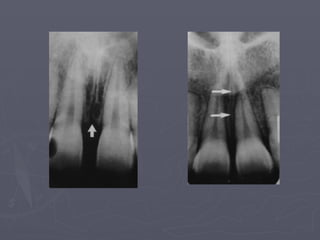

Genial Tubercles

► Also called mental spine.

► Divided right and left,

superior and inferior

promineneces.

► Appears on occlusal

radiographs.

► On peripaical radiographs

it appears as round

radiopacity surrounding

the lingual foramen.

Lingual foramen : radiolucent ‘hole ’ in centre of genial tubercles.

Lingual nutrient vessels pass through this foramen .

Genial tubercles: They appear as radio Opaque circle that

surrounds the lingual foramen just below the apices of the Of

the incisors.

Mental Foramen

► It is the anterior limit of the inferior alveolar

canal.

► It doesn’t appear on every radiograph because

its opening is directed superiorly and posteriorly.

► It may be round, oblong, slit-like or very

irregular and partially or completely

corticated.

► The foramen is seen about half way between

the lower border of the mandible and the crest

of the alveolar process usually in the region of

the apex of the second premolar.

► Misinterpreted as a periapical pathosis.

mental

foramen